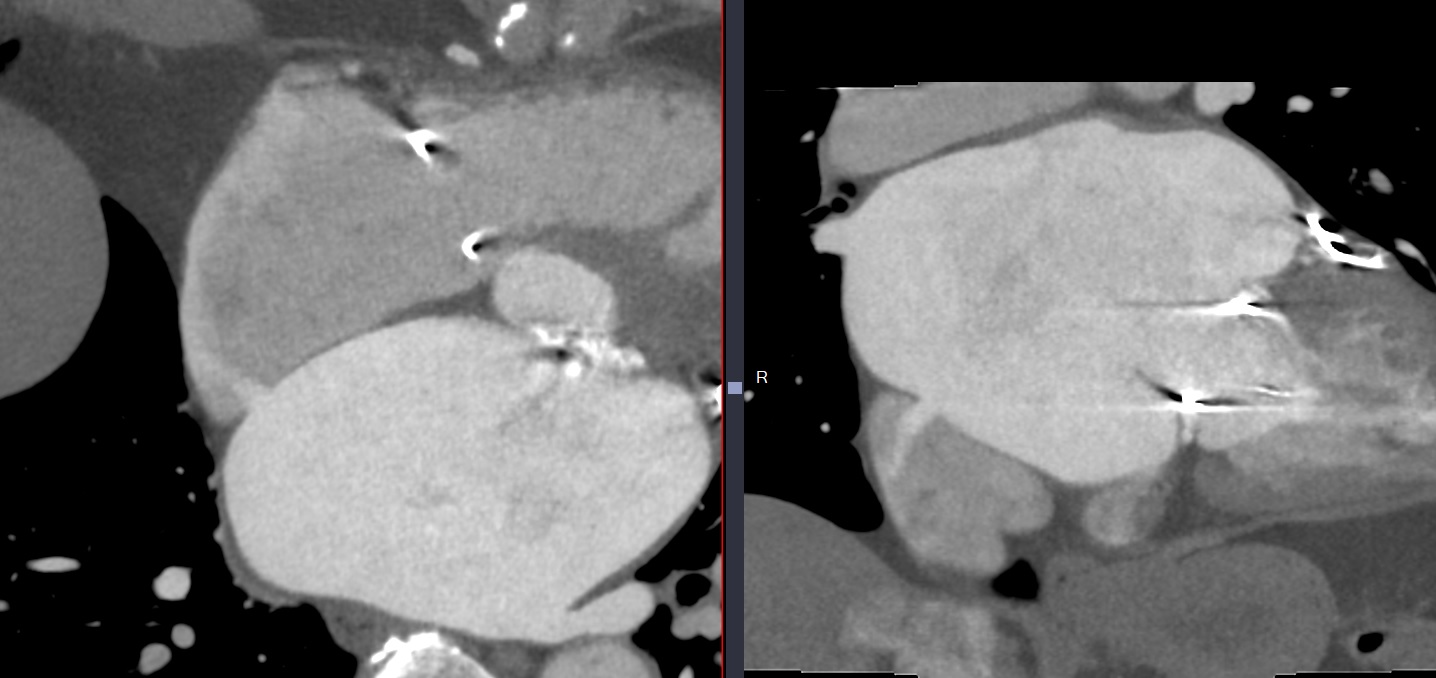

Cas

ASD paroi inférieur du septum interatrial